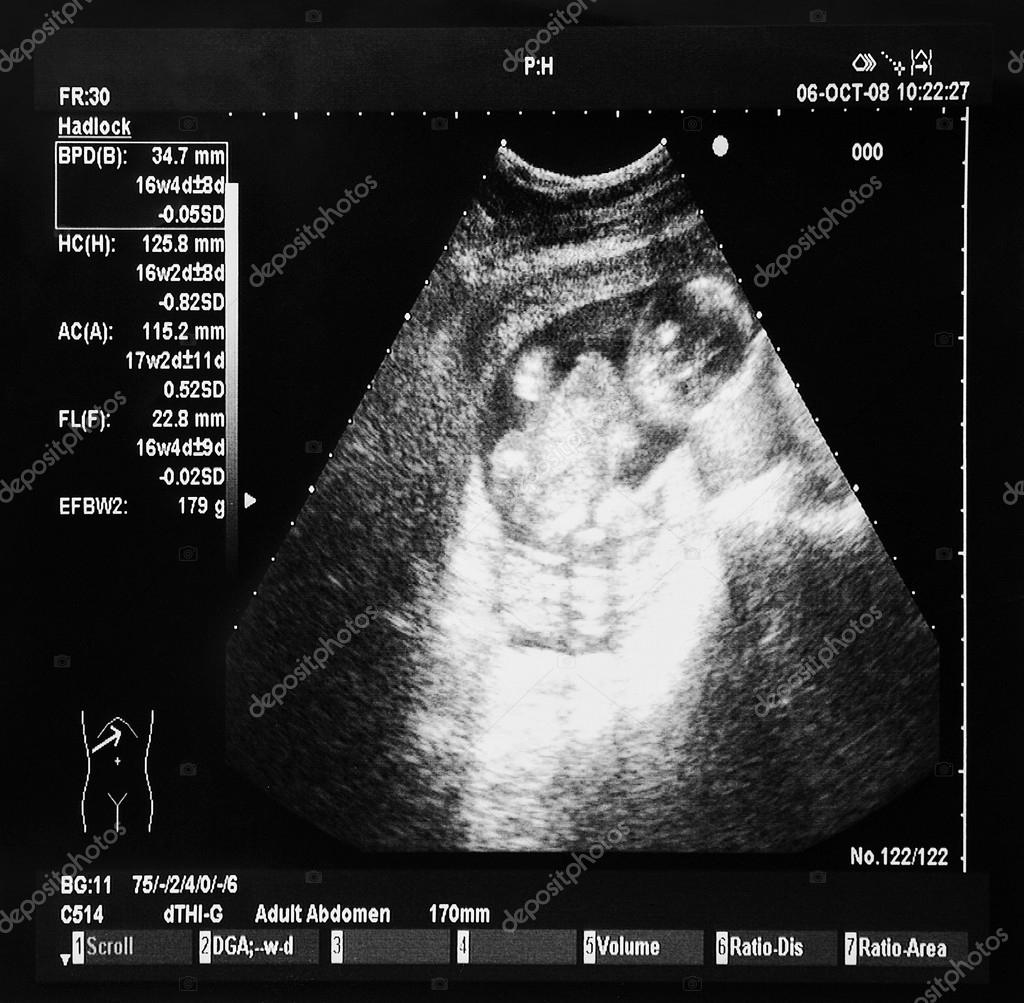

Ultrazvuk miminko — Stock Fotografie © wabeno 22412085 Petrova Ultrazvuk Cijena trudničkog ultrazvuka je 150,00kn. 25% žena oboljelo od raka ima rak dojke. U sklopu poliklinike djeluju opća ginekološka ambulanta, trudnička ambulanta, ambulanta za dijagnostički ultrazvuk, ambulanta za. Ultrazvuk dojki je idealna pretraga za djevojke i žene u reproduktivnoj dobi jer jasnije od mamografije prikazuje tkivo dojki koje ima gusto žljezdano tkivo. Smještena u zagrebu, na adresi petrova ulica 13,. Petrova Ultrazvuk.